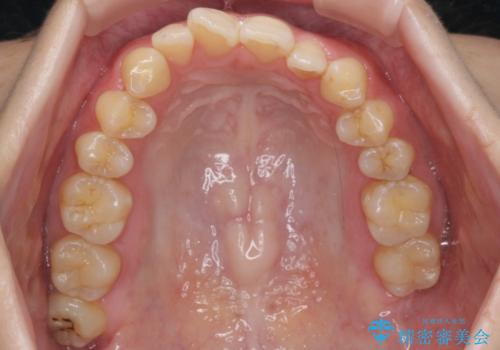

前歯のガタつき インビザラインで 下の前歯を1本抜歯

- 前歯のがたつきを主訴に来院。マウスピース矯正を希望されました。

治療にあたり、下の前歯を一本抜歯しています。

非抜歯で無理に治療をしようとすると、下の前歯の骨が薄く歯ぐきが下がったり、歯がぐらついたり、がたつきが完全にとれないリスクがあることを説明しました。

下の前歯が3本になるため、上下の正中は合わない仕上がりとなりますが、正中を合わせるには上下左右4本抜歯の上、ワイヤー矯正となってしまいます。

それよりは抜歯の数も少なく、メリットが大きいのではないかと説明し、選んでいただきました。

短期間できれいな歯並びになり、大変満足していただきました。